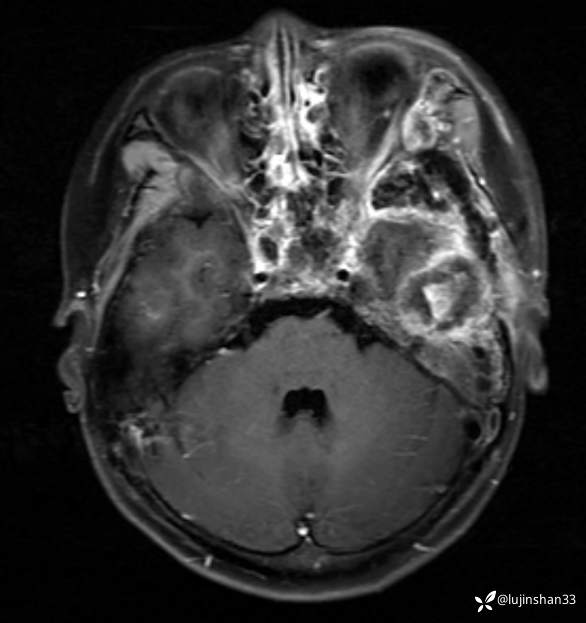

简要病史:患儿父母半年前发现患儿左颞部较右侧突起,无伴随症状,未重视未诊治,1月前,患儿左颞部肿物长大,伴头晕,向一侧倾倒感,头痛,两次剧痛,余为胀痛,偶有夜间出现左下颌区域皮肤麻木,咀嚼时左面部疼痛,10天前,患儿出现左眼睑肿胀伴疼痛,睁眼疼痛加重,不伴视力障碍,无畏寒发热,无意识障碍,无饮水呛咳,在XX同仁医院行颅脑核磁示:左侧颞下窝占位。门诊以“颞下窝占位(左)”收入院。患者目前精神状态良好,体力正常,食欲正常,睡眠正常,体重无明显变化,大便正常,排尿正常。

体格检查:左侧颞部可见约7*4cm大小肿物突起,质软,边界不清,局部皮肤无红肿,伴疼痛,左眼睑肿胀,不能睁眼,角膜反射检查不能配合。嗅觉粗测正常,双眼视力粗测正常,双侧瞳孔等大同圆,直径约3mm,对光反射灵敏。眼底检查未见异常。右眼睑无下垂,左眼睑肿胀,眼裂约4mm,无眼球下陷,眼球各方向活动自如。双面部痛温觉正常。双侧颞肌、咀嚼肌无萎缩,咀嚼动作基本对称,张口无歪斜,伸舌无偏斜。双侧额纹对称,闭眼无露白,双侧鼻唇沟无变浅,鼓腮无漏气、示齿时口角无明显偏斜。双侧咽腭弓对称,悬雍垂居中,双侧咽反射正常。声音无嘶哑,无饮水呛咳,无吞咽困难。双侧斜方肌、胸锁乳突肌均无萎缩,双侧转头、耸肩对称有力。

临床诊断:颅中窝、颞下窝小圆细胞恶性肿瘤

术后MRI:2022年2月考虑复发